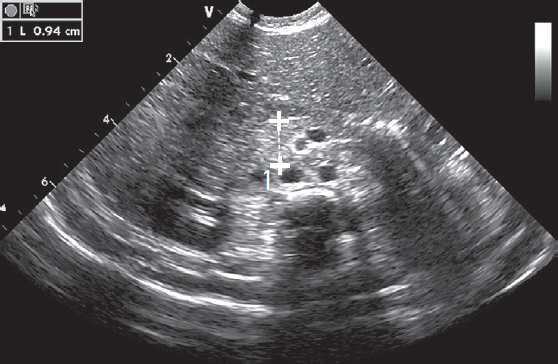

Одна из операций проведена на предмет высокой кишечной непроходимости, на УЗИ визуализировалась дилатированная двенадцатиперстная кишка — было высказано предположение о ее атрезии (рис. 7). Операция прошла без предварительного рентгенологического дообследования. При ревизии купол слепой кишки оказался высоко фиксирован эмбриональными тяжами к двенадцатиперстной кишке, тонкая и толстая кишка имели общую брыжейку, кишка спавшаяся, брыжейка перекручена на 180о. Тупо и остро разделены эмбриональные тяжи. При выделении от тяжей двенадцатиперстной кишки выявлена кольцевидная поджелудочная железа, фиксировавшая и сужавшая просвет кишки.

Рис. 7. Пример расширения двенадцатиперстной кишки у новорожденного на УЗИ, В-режим (слева). Второй сегмент двенадцатиперстной кишки у здорового новорожденного (справа)

Fig. 7. Example of duodenal dilatation in a newborn on ultrasound, B-mode (left). Second segment of the duodenum in a healthy newborn (right)